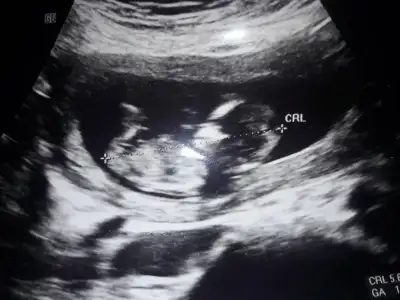

Kaç haftalık erkek dedi dr ben hala kız diyorum dünde baktım bu USG kız gibi nubu

Kaç haftalık erkek dedi dr ben hala kız diyorum dünde baktım bu USG kız gibi nubu 🙈 sağlıkla gelsin minnos 🧿

Şimdi 12+6ydı son gittiğimde. Erkek dedi, güncel resim budur. Benim ilk olduğu için çok farketmiyor aslında sırf merak :))

• CF3FF9A1-ADB7-4C3C-B39E-99E95A1D023C.webp

CF3FF9A1-ADB7-4C3C-B39E-99E95A1D023C.webp

19,1 KB · Görüntüleme: 80

Aaa evet burda kabarık birazda çokta net değil sağlıkla gelsin minnos 🧿